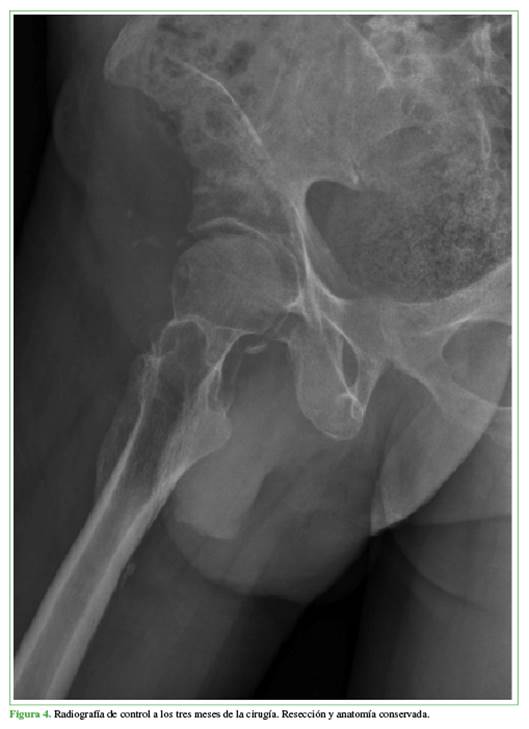

En el seguimiento radiográfico inmediato y a los tres meses de la cirugía (Figuras 3 y 4), se confirmó la resección completa de la osificación. Clínicamente, al año de la cirugía, el paciente tenía una notable mejora en los arcos de movilidad, con extensión completa y flexión de 110°. Además, logró retomar la marcha con la ayuda de un caminador. Continúa con terapia física y fortalecimiento del cuádriceps bajo la supervisión de Fisiatría, sin dolor ni complicaciones adicionales hasta la fecha.